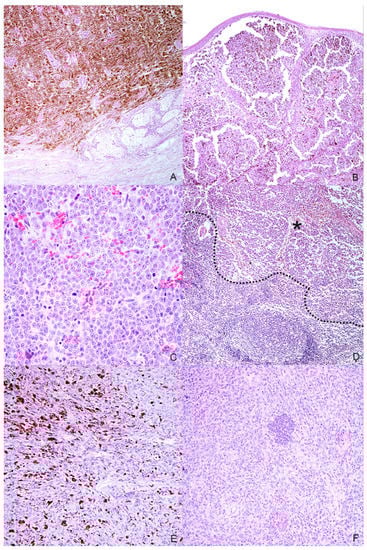

Figure 2.

Histopathologic characteristics of the selected melanocytic tumors. (A) Case n. 1—Dermal highly cellular proliferation of pigmented melanocytes with minimal cellular atypia (H-E, 100×); (B) Case n. 2—Densely packed, moderately pigmented melanocyte proliferation infiltrating the lamina propria of the oral mucosa(H-E, 100×); (C) Case n. 3—Mucosal amelanotic melanoma: cells show large nuclei with prominent nucleoli without intracytoplasmic melanin. Note the high mitoses (H-E, 400×); (D) Case n. 3—Lymph node metastasis: the same atypical melanocytic population effacing the architecture of the lymph node (residual cortical tissue on the bottom-left of the dotted line; metastatic tumoral tissue on the asterisk) (H-E, 100×); (E) Case n. 4—Spindle-shaped, frequently pigmented melanocytes proliferation with moderate cellular atypia, localized in the dermis (H-E, 200×); (F) Case n. 5—Mucosal amelanotic melanoma: epithelioid to polygonal neoplastic melanocytes forming sheets and rare nests in the lamina propria (H-E, 200×).

Eight samples were initially collected; however, three cases were excluded during processing because the subsequent histological and immunohistochemical investigations did not confirm the melanocytic origin of the tumor, diagnosed cytologically. Anamnestic data and histological classification of the selected five cases are reported in Table 1. Of the 5 cases, 2 were mixed breed and other 3 dogs were purebred dogs (English setter, German shepherd and Dobermann); 2 dogs were male and 3 female. Cutaneous tumors were localized in the interdigital space and flank, while mucosal ones originated from different sites of the oral cavity and the labial mucosa (Figure 1). Histology supported the melanocytic origin of the tumors and 1 cutaneous melanocytoma, 1 cutaneous melanoma and 3 mucosal melanoma were identified (Figure 2). Immunohistochemical investigation with antibodies against Melan A and PNL2 confirmed the morphological diagnosis in formalin-fixed, paraffin-embedded tissues. At the time of surgical excision of the tumor, only one dog with a mucosal melanoma (Case n. 3) had metastases to the mandibular and retropharyngeal lymph nodes.